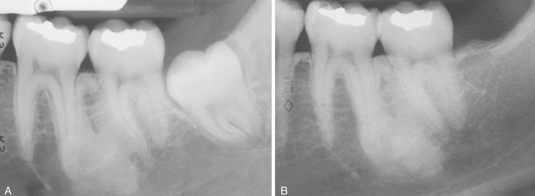

focal osteoporotic marrow defect

likely filled with blood

no epithelial lining

aneurysmal bone cyst